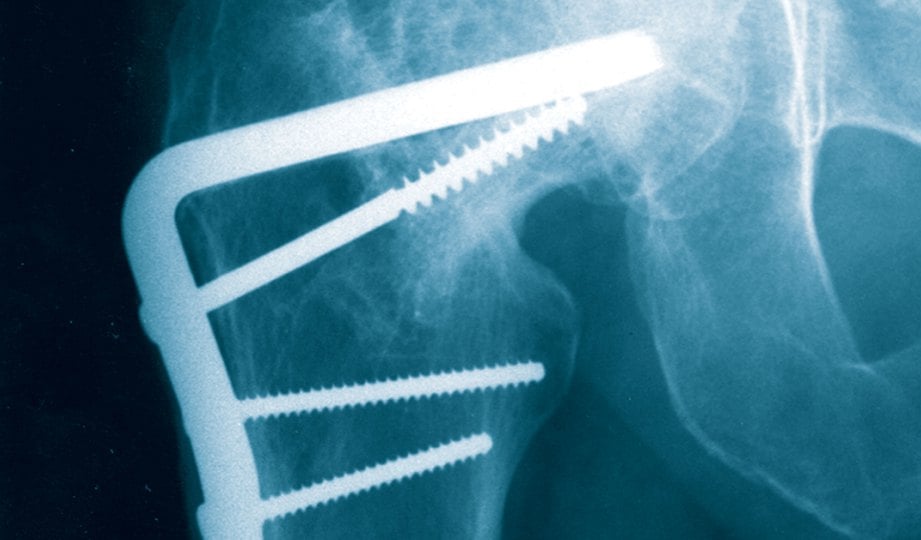

Perlukah membuang besi atau implan? û Dr Ahmad Mahyuddin | The Malaysian Medical Gazette

Perlukah membuang besi atau implan? û Dr Ahmad Mahyuddin | The Malaysian Medical Gazette

Plat Logam Pasca Fraktur : Perlu Diangkat Atau Tidak - Alomedika

Plat Logam Pasca Fraktur : Perlu Diangkat Atau Tidak - Alomedika